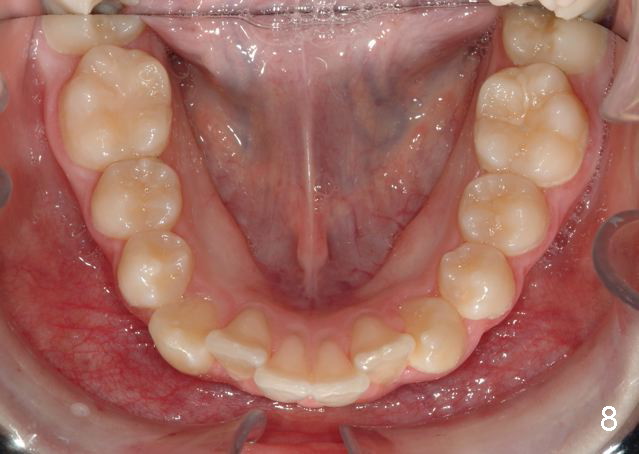

Before